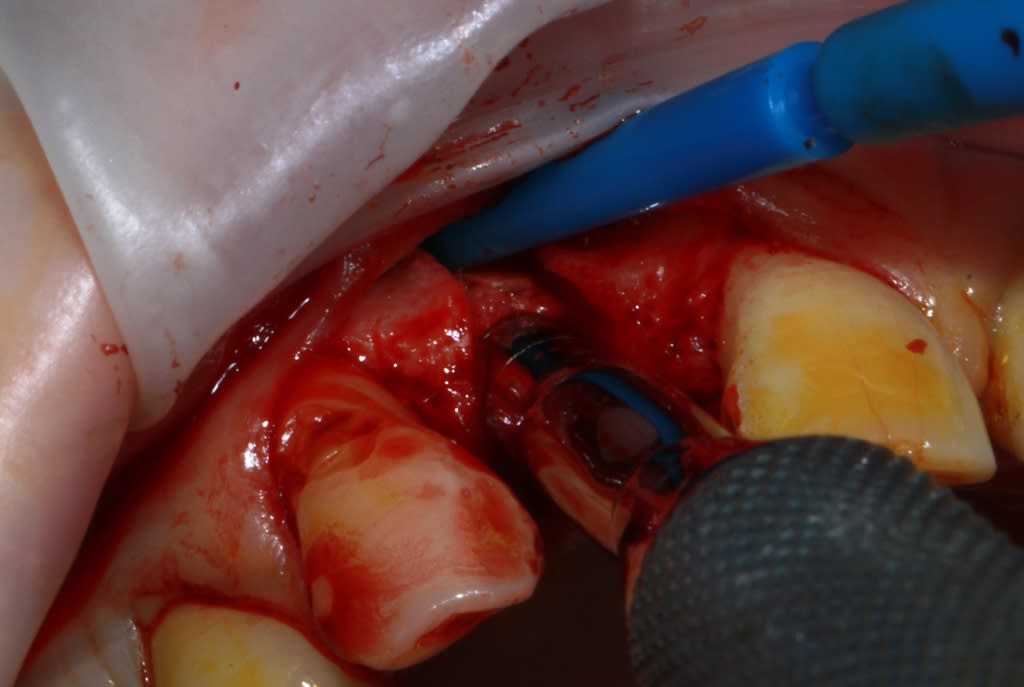

Thomas, tu as un plan pour guider dans un cas comme ça?

ou comment remplacer 12 avec soucis vestibulaire, par un implant, sans greffe, sans ROG, juste avec les mimines....?

vue de l’intérieur..

Une question, tu utilise une lame 11, que tu tapes avec un maillet, j'imagine. Jamais de fracture de la pointe?

Non jamais de fracture de la pointe...à part en TP et plutôt fracture à la base de la fixation sur le manche...

Soit lame 11 soit 15 ça dépend de l'os